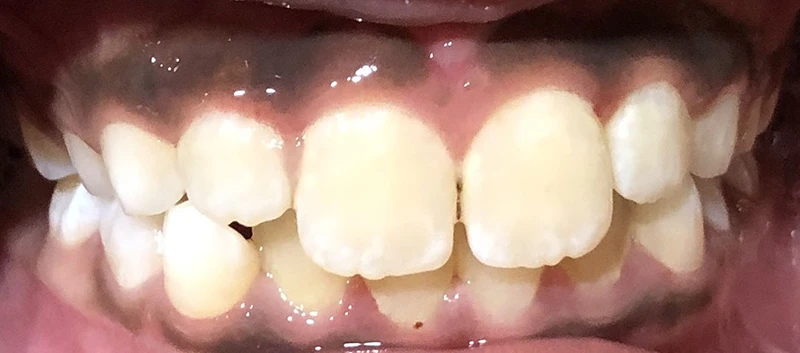

Actual Patient: Leanna

Img Before 2 2 Img After 2 1

Severe “Overbite”, BUCK TEETH, Narrow Jaws, Severe Deep Bite, Mouth breathing

Leanna Before 1 Leanna After 1 1

7.5 months

Front View

Top View

Right & Left Sides